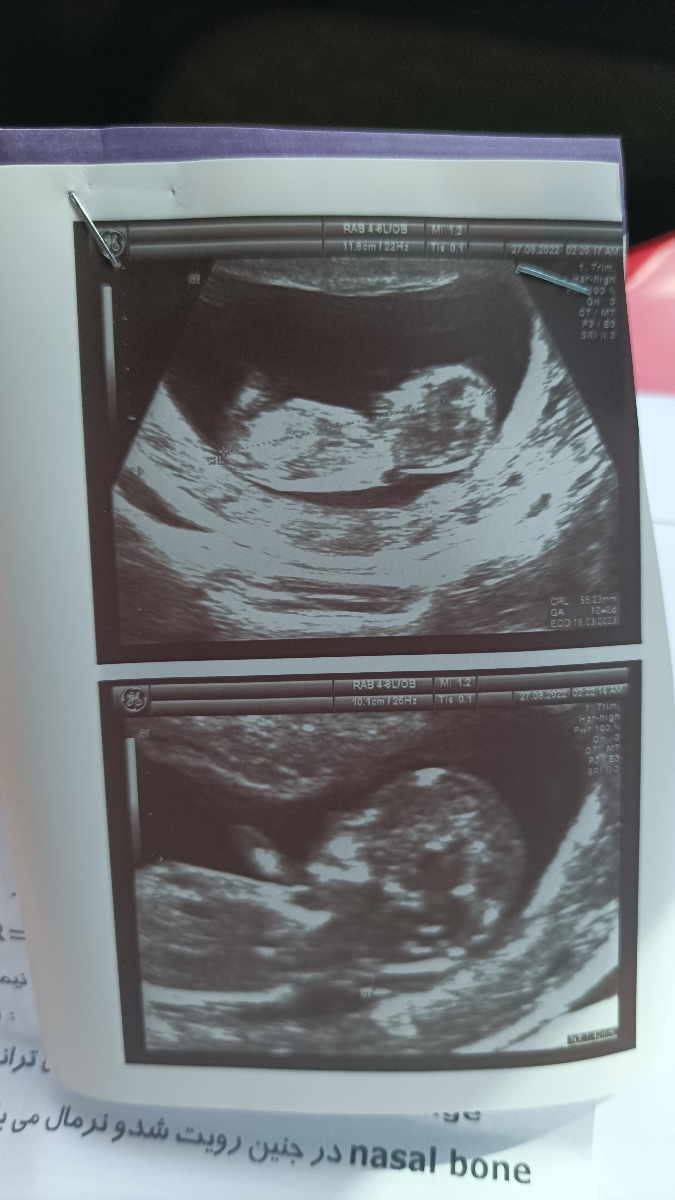

سلام سونوی ان تی من سالمه؟

برا سونو ان تی خانم رنجبر فک کنم همه چی خوب باشه

هر دو را انجام دهید، البته اول باید سونوگرافی انجام شود و بعد با نتیجه آن همان روز یا در طی کمتر از 24 ساعت آزمایش خون غربالگری نیز انجام شود، زیرا سونوگرافی نمیتواند مشکلات ژنتیکی را ارزیابی کند.

پزشک شما فقط سونوگرافی را نوشته که احتمالا بر اساس قوانین جدید است که به نفع مادر و جنین نیستند و با هدف افزایش جمعیت به هر قیمتی حتی با جنین بیمار طراحی شده اند شما خودتان از پزشک بخواهید بخش خون غربالگری را درخواست کند🌹